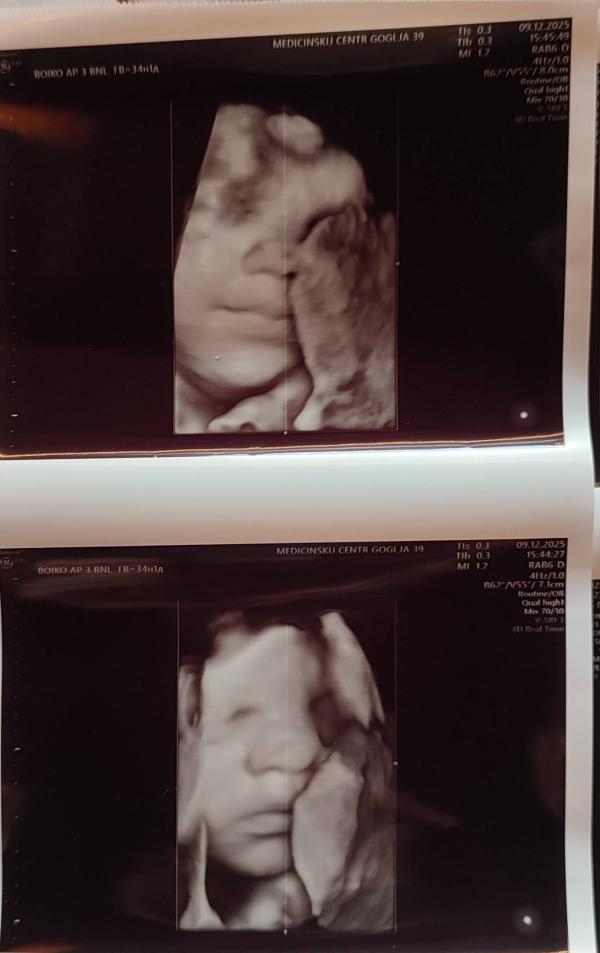

Ну какой же милашка☺улыбается, очень на доченьку похож❤Бабенко сказала, что ничего не увидела критичного, придраться не к чему. 2570 вес поставили, будет большой мальчик

На первом фото прям такая улыбка блаженная 😍

Да, третий скрининг) У него ещё такая моська хитрая была, не хотел личико показывать, то в плаценту упёрся носом, то ручками закрылся, мы обрадовались, что ручки убирает, так он ещё ногу задрал и улыбается, типо ничего вам не покажу😄